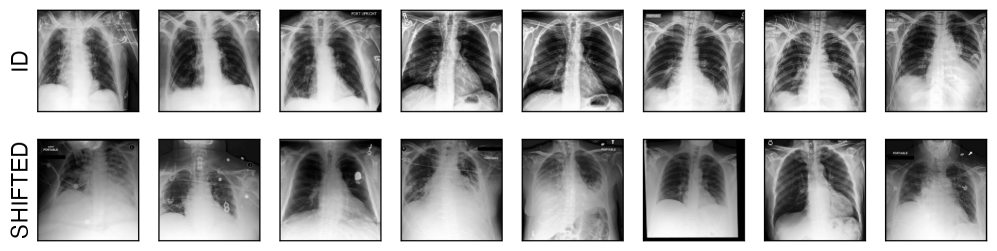

We analyse calibration robustness across different image classification tasks and real-world natural distribution shifts. First, we investigate robustness against geographic and sub-population shifts, in natural image classification using the Living17 and Entity30 datasets (Santurkar et al., 2020), as well as Wilds-iCam (Koh et al., 2021). Next, we analyse realistic shifts specific to medical imaging, a high-stakes domain where robustness and calibration are of particular importance. We study calibration robustness against: (i) scanner changes in breast density assessment models using the EMBED (Jeong et al., 2023) mammography dataset, (ii) scanner, population and prevalence changes in chest X-ray classification (No Finding / Diseased) using CheXpert (Irvin et al., 2019) and MIMIC-CXR (Johnson et al., 2019) (CXR), (iii) equipment, prevalence, and geographic location changes for diabetic retinopathy assessment models, combining multiple public fundus imaging datasets (Karthik & Sohier, 2019; Decencière et al., 2014; Dugas et al., 2015) (RETINA), and (iv) staining protocols changes in histopathology, using WILDS-CameLyon (Koh et al., 2021). Finally, we test against hard modality shifts in natural image classification using DomainNet (Peng et al., 2019) with ‘Real’ images as the ID domain. Details about datasets and ID/shifted domain definitions can be found in Appendix˜A.1, including visual examples of samples from both ID and shifted test sets for each dataset.

In this work we study realistic shifts in the medical imaging and natural images domain. For this we leverage multiple public datasets across various modalities and tasks. We here detail how we defined ID and OOD domains for non-standard benchmark datasets. We summarise splits and ID/shifted domains definitions in Table˜A.1. In Figs.˜A.1 and A.2 we illustrate the types of shift by showing examples of images from both the ID and the shifted sets for each dataset.

CXR

we analyse robustness against scanner, location and label distribution changes in chest-xray classification models (No Finding versus Disease task) using the CheXpert (Irvin et al., 2019) and MIMIC-CXR (Johnson et al., 2019) datasets. We use the CheXpert dataset as our ID domain, splitting randomly between train/val/test at the patient level, and we use a random subset of 25,000 images from the MIMIC-CXR database as our OOD test set.